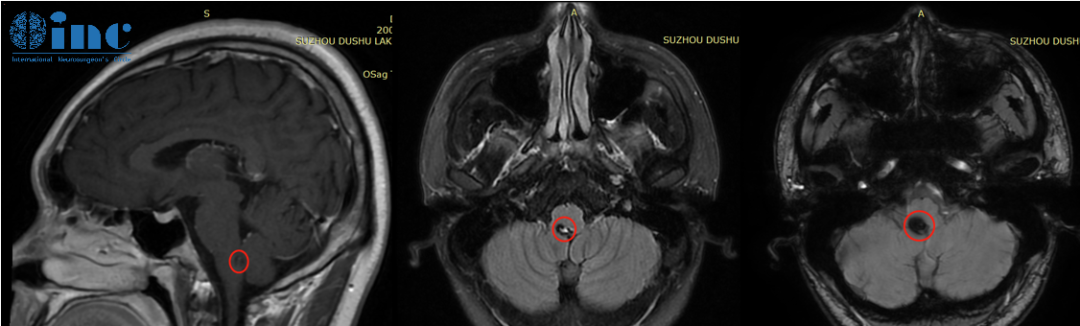

但是却不想竟是“生命中枢”——脑干上出了问题。头部CT显示延髓后方近小脑见大小约6.8*9.9mm的片状高密度阴影,怀疑脑干海绵状血管瘤。